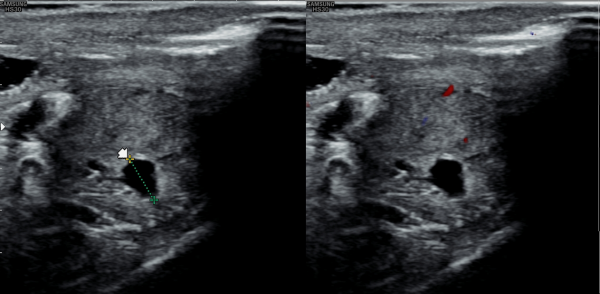

5년전부터 폐암으로 투병중 전립선 치료를 받지 못하던중 최근 하복부 통증이 심해져 내원 당일 추적 경직장 전립선 초음파 추적 검사상

전립선 낭종들이 커지고 사정관 입구의 미세 결석이 관찰되는 사진입니다.

A follow-up transrectal prostate ultrasound image taken on the day of the visit shows enlargement of prostatic cysts and microcalcifications at the opening of the ejaculatory duct in a patient who had been unable to receive prostate treatment due to lung cancer for the past five years and recently developed worsening lower abdominal pain.